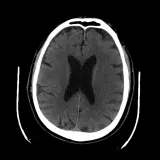

Over 2,100 interactive radiology cases, curated by radiologists for your level of training. Scroll, window, and view cases full screen — just like on PACS. Click linked findings in each writeup to jump straight to them on the image. Cases include sample reports, a focused discussion section, original illustrations, and videos.

Our site includes 3 main courses: Call Preparation, Introduction to Radiology, and Neuro Fellowship.

Call Preparation — our comprehensive curriculum for junior residents preparing for call covering both classic and atypical presentations. Use the call simulator to practice a real call shift — shuffle cases, enter your own preliminary report, and receive constructive AI feedback.

Neuro Fellowship — a course tailored for fellows and practicing radiologists with in-depth reviews of advanced neuro topics like brain tumors, featuring rare diagnoses, differentials, and clinical pearls.